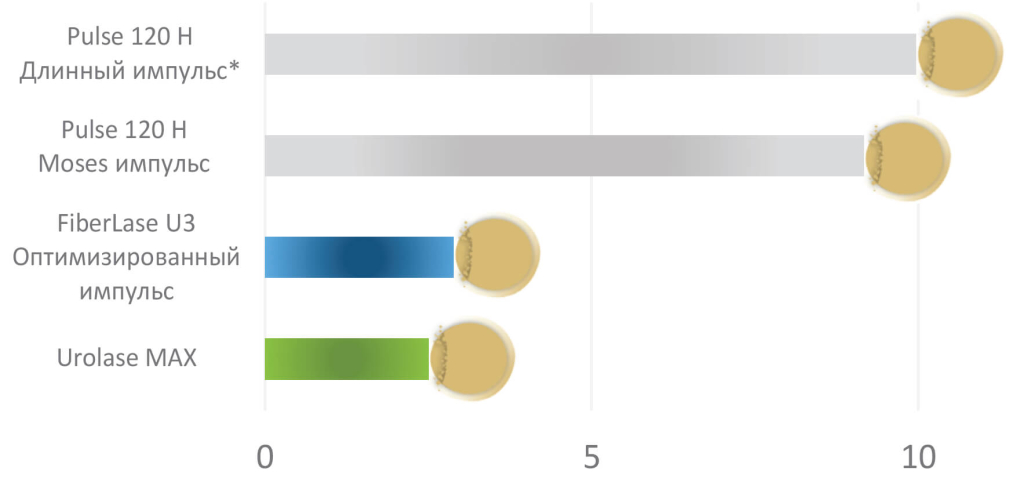

Режим MRP - минимальная ретропульсия конкремента при дроблении по сравнению с гольмиевыми лазерами и стандартными импульсами тулиевых волоконных лазеров серии FiberLase. Режим был ранее доступен только в топовом лазере FiberLase U-MAX, теперь и в базовом аппарате UROLASE+

Модулированные импульсные настройки и высокие мощностные характеристики лазерного аппарата Urolase MAX выводят литотрипсию на качественно новый уровень эффективности, отличный от всех урологических лазеров.Режим MRP — минимальная ретропульсия конкремента при дроблении по сравнению с гольмиевыми лазерами и стандартными импульсами тулиевых волоконных лазеров серии FiberLase.